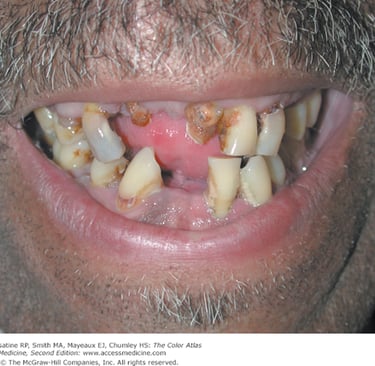

Children's dental health in El Salvador faces significant challenges, with high rates of untreated early childhood caries (tooth decay) linked to chronic exposure to sugary drinks and snacks, which are often cheaper than safe drinking water. Lack of education about proper oral hygiene, limited access to dental care, and socio-economic factors contribute to a cycle of decay, pain, and malnutrition. Community-based interventions including education, and distribution of oral care products show promise but face limitations and challenges.

The dental situation for adults in El Salvador is challenging, characterized by widespread tooth loss (edentulism) and periodontal disease. Poor oral hygiene is a contributing factor, linked to factors such as diets high in sugar and lack of access to proper dental education.